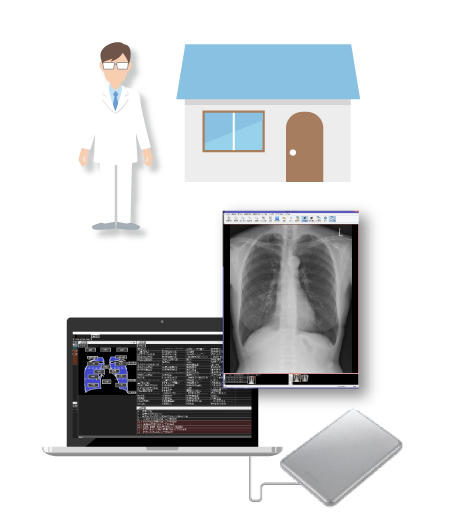

外部読影も簡単にシステム化したい!

- セキュリティ機能付きのメディアを使い、外部でもレポート入力可能

- ネットワークも事前のソフトウェアインストールも不要!手軽に読影開始

- メディアからビューア&レポートが起動し、自宅や勤務先のPCで所見入力

- ネットワーク環境下では、オンラインでのデータ授受も可能

オフラインレポート

データ+システム

(セキュリティ機能付き)

急な医師の交代や、環境の変化にも簡単に対応可能。

外部に多く読影依頼している施設は必見です!